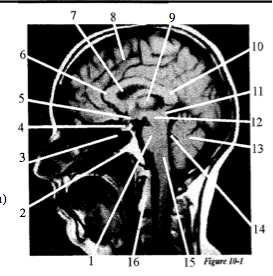

Question 1

Question

Label with just the letter A. Fourth ventricle, B. Pituitary gland, C. Cerebellum, D. Clivus, E. Cerebrum, F. Quadrigeminal body, G. Pons, H. Lateral ventricle, I. Medulla oblongata, J. Sphenoid sinus, K. Optic chiasm, L. Corpus callosum (genu), M. Corpus callosum (splenium), N. C-2, O. Thalamus, P. Cerebral peduncle

Answer

• G

• D

• J

• B

• K

• L

• H

• E

• O

• M

• F

• P

• C

• A

• I

• N